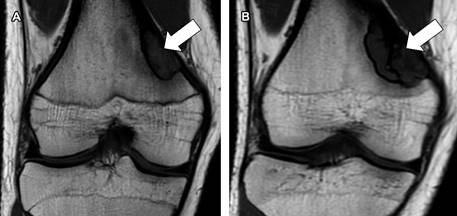

A la exploración física existe leve dolor a la palpación en la cara medial de ambos muslos. Se realizó resonancia magnética a nivel de ambas rodillas (Figuras 1B y 2C), en la cual se confirmó la presencia de fibroma no osificante en ambas rodillas, además se comparó con estudios previos del 2020 (Figura 2A) y 2022 (Figuras 1A y 2B).

Figura 1: Resonancia magnética de la rodilla derecha en plano coronal, secuencia T1. A) Año 2022. B) Año 2024. Se observa un fibroma no osificante localizado en la porción posterior y medial de la diáfisis femoral (flecha blanca).

En este paciente, es de interés la existencia de dos fibromas no osificantes, uno en cada fémur (Figuras 1 y 2), además del dolor que llega a limitar su actividad física, lo cual podría estar en relación con el crecimiento progresivo que han tenido las lesiones: en el fémur derecho en el 2022 (Figura 1A) la lesión medía 2.4 × 1.1 cm en sus ejes mayores y en el 2024 (Figura 1B) mide 3.3 × 1.9 cm; en el fémur izquierdo en el 2020 (Figura 2A) la lesión inicialmente detectada tenía dimensiones de 1.3 × 0.8 cm, en el 2022 (Figura 2B) con medidas de 3 × 1 cm y en el 2024 (Figura 2C) con ejes mayores de 3.5 × 1.2 cm.